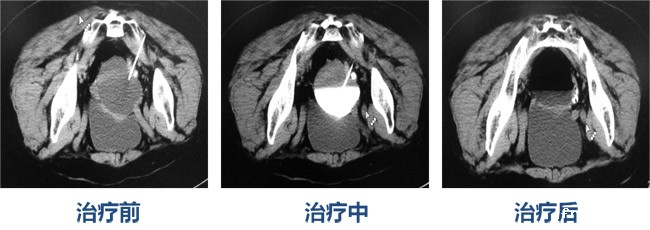

以下是成功病例的CT影像对比:

女,49岁,双肾多发囊肿术后复发CT引导聚桂醇硬化治疗

女,76岁, 左侧卵巢囊肿CT引导下囊肿聚桂醇硬化术